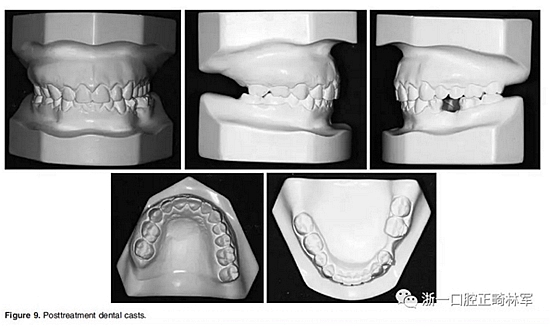

在治療結(jié)束時(shí),面部基本對(duì)稱(Figure 7)。上中線與面中線重合,下中線向左偏0.5mm,傾斜的合平面得到矯正,獲得了良好的咬合關(guān)系,具有正常的覆合和覆蓋,留下7mm的空間用于植入左下前磨牙(Figure 8、9)。